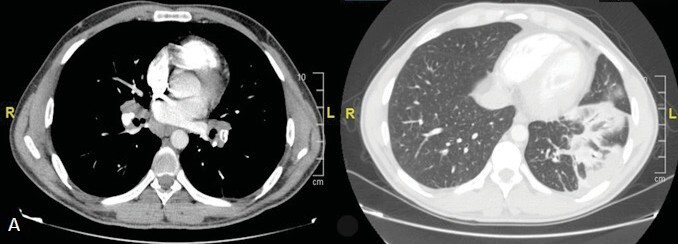

Tuberculosis (TB) is an airborne infectious disease caused by Mycobacterium tuberculosis (MTB). Although it typically affects the lungs (pulmonary TB), one-fifth of TB cases present as extrapulmonary TB. The diagnosis of extrapulmonary TB is often overlooked due to its atypical clinical and radiological manifestations. Differentiating TB from neoplastic conditions poses significant challenges. A 33-year-old female patient was admitted to the emergency clinic with shortness of breath, cough, and abdominal pain. Postero-anterior chest X-ray revealed massive pleural effusion leading to mediastinal shift. With a preliminary diagnosis of malignant pleural effusion, a pleural catheter was inserted, and the patient was referred for a positron emission tomography (PET/CT) to assess the primary site and the optimal location for a biopsy. The PET/CT revealed asymmetric soft tissue thickening on the left side of the nasopharynx, and increased fluorodeoxyglucose (FDG) uptake in the left cervical lymph nodes raised suspicion regarding primary nasopharyngeal cancer. Additionally, there was an increased FDG uptake observed in the mass lesion located in the right upper lobe, mediastinal lymph nodes, pleural surfaces in the left hemithorax, perihepatic areas, and peritoneum, indicating diffuse metastatic disease. Tuberculosis diagnosis was confirmed through biopsies demonstrating granulomatous inflammation in the lung and nasopharynx, along with culturing MTB from pleural effusion. Positron emission tomography played a crucial role in identifying sites of TB involvement. Despite its rarity, healthcare professionals should consider nasopharyngeal TB as a potential diagnosis when evaluating nasopharyngeal masses.